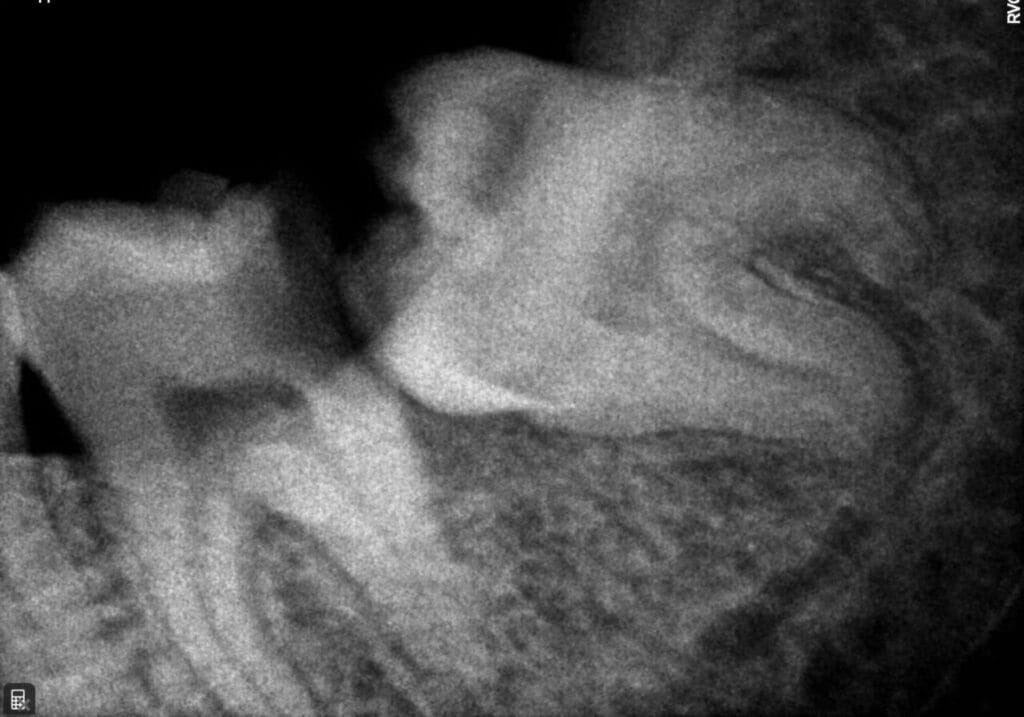

X-Ray

X rays are an important Diagnostic tool. We use AERB certified Digital X-ray equipment in our premises.